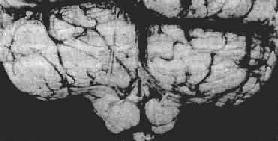

<a href=海马钩回疝"/>

图16-7 海马钩回疝

海马回内侧肿胀有深切迹(箭头),中脑右移变形,中脑右大脑脚受压,局部坏死出血(Kemohan切迹)